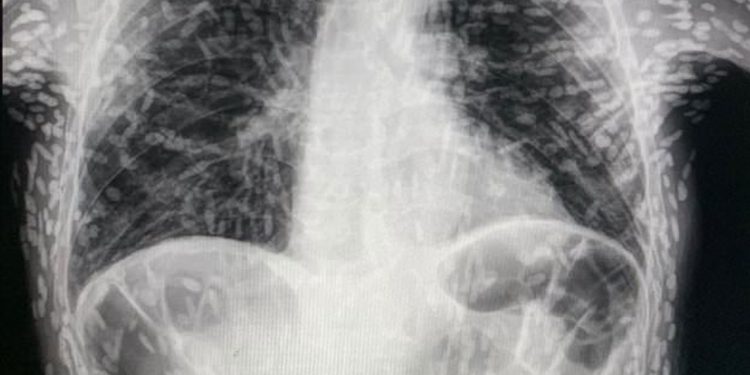

தொடர் இருமலுக்காக சிகிச்சை பெற வேண்டி மருத்துவமனையை அணுகியுள்ள ஒருவர் எடுத்த எக்ஸ்-ரே ஸ்கேனின் புகைப்படம் ஒன்று இணையத்தில் வைரலாகிவருகிறது. பார்த்தாலே திகிலில் உறைந்துதுபோகவைக்கும் அளவிற்கு அந்தப் புகைப்படம் அருவருப்பையும், அதே சமயம் அதிர்ச்சியையும் தருகிறது.

பிரேசில் நாட்டைச் சேர்ந்த அந்த நபரின் உடலுக்குள் வெள்ளை நிறத்தில் ஏதோ புள்ளிகள் போன்ற உருவம் படர்ந்திருப்பது புகைப்படத்தில் தெரிகிறது. அது வேறொன்றுமில்லை. பாரசைட் என்று சொல்லப்படும் ஒருவகை ஒட்டுண்ணிப் புழு தான். இந்த நிலைக்கு சிஸ்டிசெர்கோசிஸ் என்று பெயரிடப்பட்டுள்ளது.

இவ்வாறான லார்வாப் புழுக்கள் பரவலின்போது தலைவலி, வலிப்பு, குழப்ப மனநிலை, தலைச்சுற்றல் மற்றும் மூளையில் அதிக நீரை உருவாக்கும் ஹைட்ரோசெபாலஸ் போன்ற பிரச்சினைகளை உண்டாக்கும் என்று இப்புகைப்படங்களை வெளியிட்ட மருத்துவர் விட்டர் போரின் தெரிவிக்கிறார். மேலும் இவை கண்களை அடையும்போது பார்வையை மங்கலாக்கவும் செய்யலாம் என்று அவர் தெரிவிக்கிறார்.

உலகின் சில பகுதிகளில் ஏற்படும் கால்-கை வலிப்பு நிகழ்வுகளில் 70% பாதிப்புகளுக்கு மூளையில் வளரும் டேனியா சோலியம் என்ற லார்வா நீர்க்கட்டிகளே காரணமாக இருப்பதாக உலக சுகாதார நிறுவனம் தெரிவிக்கிறது. ஆண்டுக்கு சுமார் 2.5 மில்லியன் மக்கள் டேனியா சோலியம் நோயால் பாதிக்கப்படுவதாகக் கருதப்படுகிறது. இது பொதுவாக ஆசியா, தென் அமெரிக்கா மற்றும் கிழக்கு ஐரோப்பாவின் ஏழ்மையான மக்கள் வாழும் பகுதிகளில் கண்டறியப்படுகிறது.